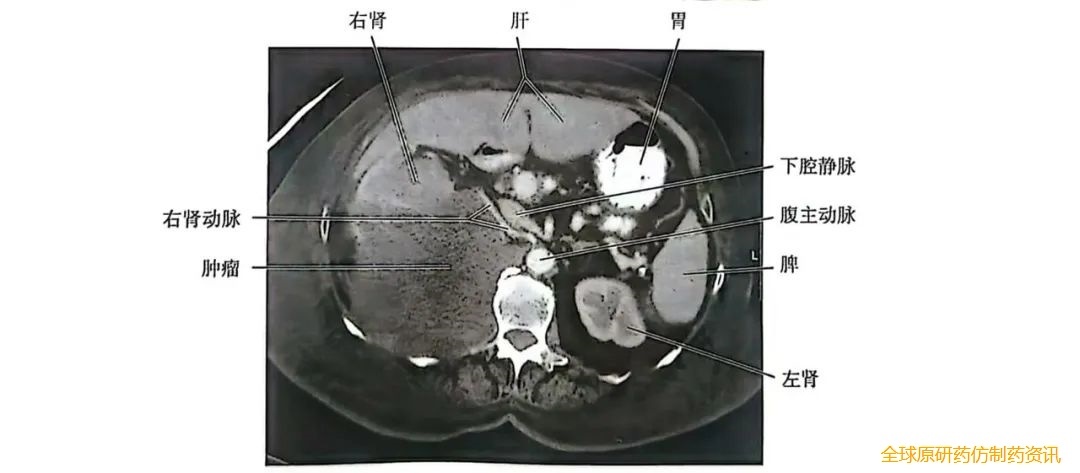

如果CT影像显示腹膜后有一个较大的肿瘤,且这个肿瘤已侵犯到下腔静脉和右肾(图2),那么就需要在进行肾切除术前对肾功能进行评估,并咨询血管科医生以规划血管切除手术。

图2 肿瘤CT扫描